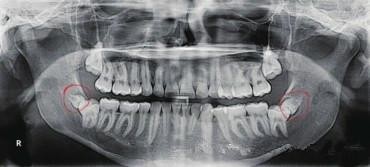

4、阻生智齿必须拔除。智齿是人类进化中逐渐退化的牙齿,临床建议智齿可以拔除,当然如果智齿位置合适有对颌牙,可以选择拔除。但是想阻生智齿必须拔除,一来阻生智齿容易引起牙齿炎症给自己带来疼痛感,二阻生智齿在生长的过程中可能会严重影响邻牙的健康,三阻生智齿如果迫近血管,在生长过程可能会出现危险。